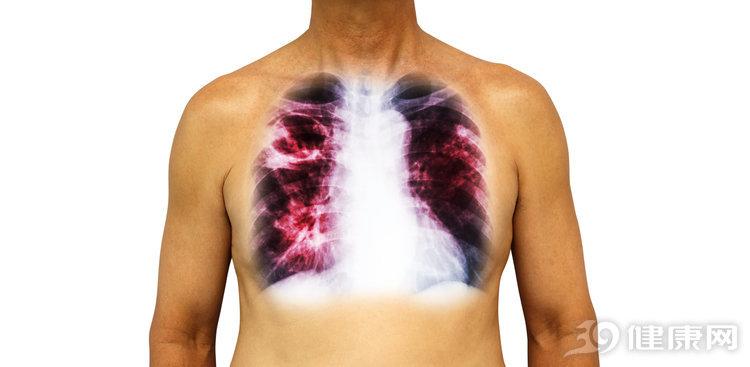

答案是确定的。艾滋病的病原体就是人类免疫缺陷病毒,这意味着艾滋病人免疫系统功能不如正常人,身体的防线更容易被外界的病毒和细菌打破,因此更容易感染肺炎、肺结核、弓形虫病等疾病。